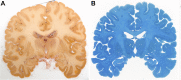

Post mortem magnetic resonance imaging (MRI) studies on the human brain are of great interest for the validation of in vivo MRI. It facilitates a link between functional and anatomical information available from MRI in vivo and neuroanatomical knowledge available from histology/immunocytochemistry. However, linking in vivo and post mortem MRI to microscopy techniques poses substantial challenges. Fixation artifacts and tissue deformation of extracted brains, as well as co registration of 2D histology to 3D MRI volumes complicate direct comparison between modalities. Moreover, post mortem brain tissue does not have the same physical properties as in vivo tissue, and therefore MRI approaches need to be adjusted accordingly. Here, we present a pipeline in which whole-brain human post mortem in situ MRI is combined with subsequent tissue processing of the whole human brain, providing a 3-dimensional reconstruction via blockface imaging. To this end, we adapted tissue processing procedures to allow both post mortem MRI and subsequent histological and immunocytochemical processing. For MRI, tissue was packed in a susceptibility matched solution, tailored to fit the dimensions of the MRI coil. Additionally, MRI sequence parameters were adjusted to accommodate T1 and T2∗ shortening, and scan time was extended, thereby benefiting the signal-to-noise-ratio that can be achieved using extensive averaging without motion artifacts. After MRI, the brain was extracted from the skull and subsequently cut while performing optimized blockface imaging, thereby allowing three-dimensional reconstructions. Tissues were processed for Nissl and silver staining, and co-registered with the blockface images. The combination of these techniques allows direct comparisons across modalities.